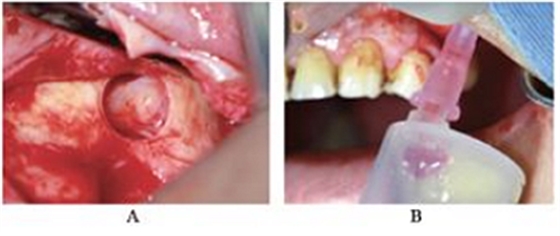

CBCT示:上颌窦内见液平面约达窦腔1/3(考虑为冲洗液未吸干净),上颌窦垂直高度得到补足,26牙高度8.4mm,27牙高度为9.5mm(图3)。患者拒绝穿刺液送病理检查。

图3 上颌窦外提升术后CBCT。

注:A,矢状面;B,26颊舌向切面;C,27颊舌向切面;D,28颊舌向切面。